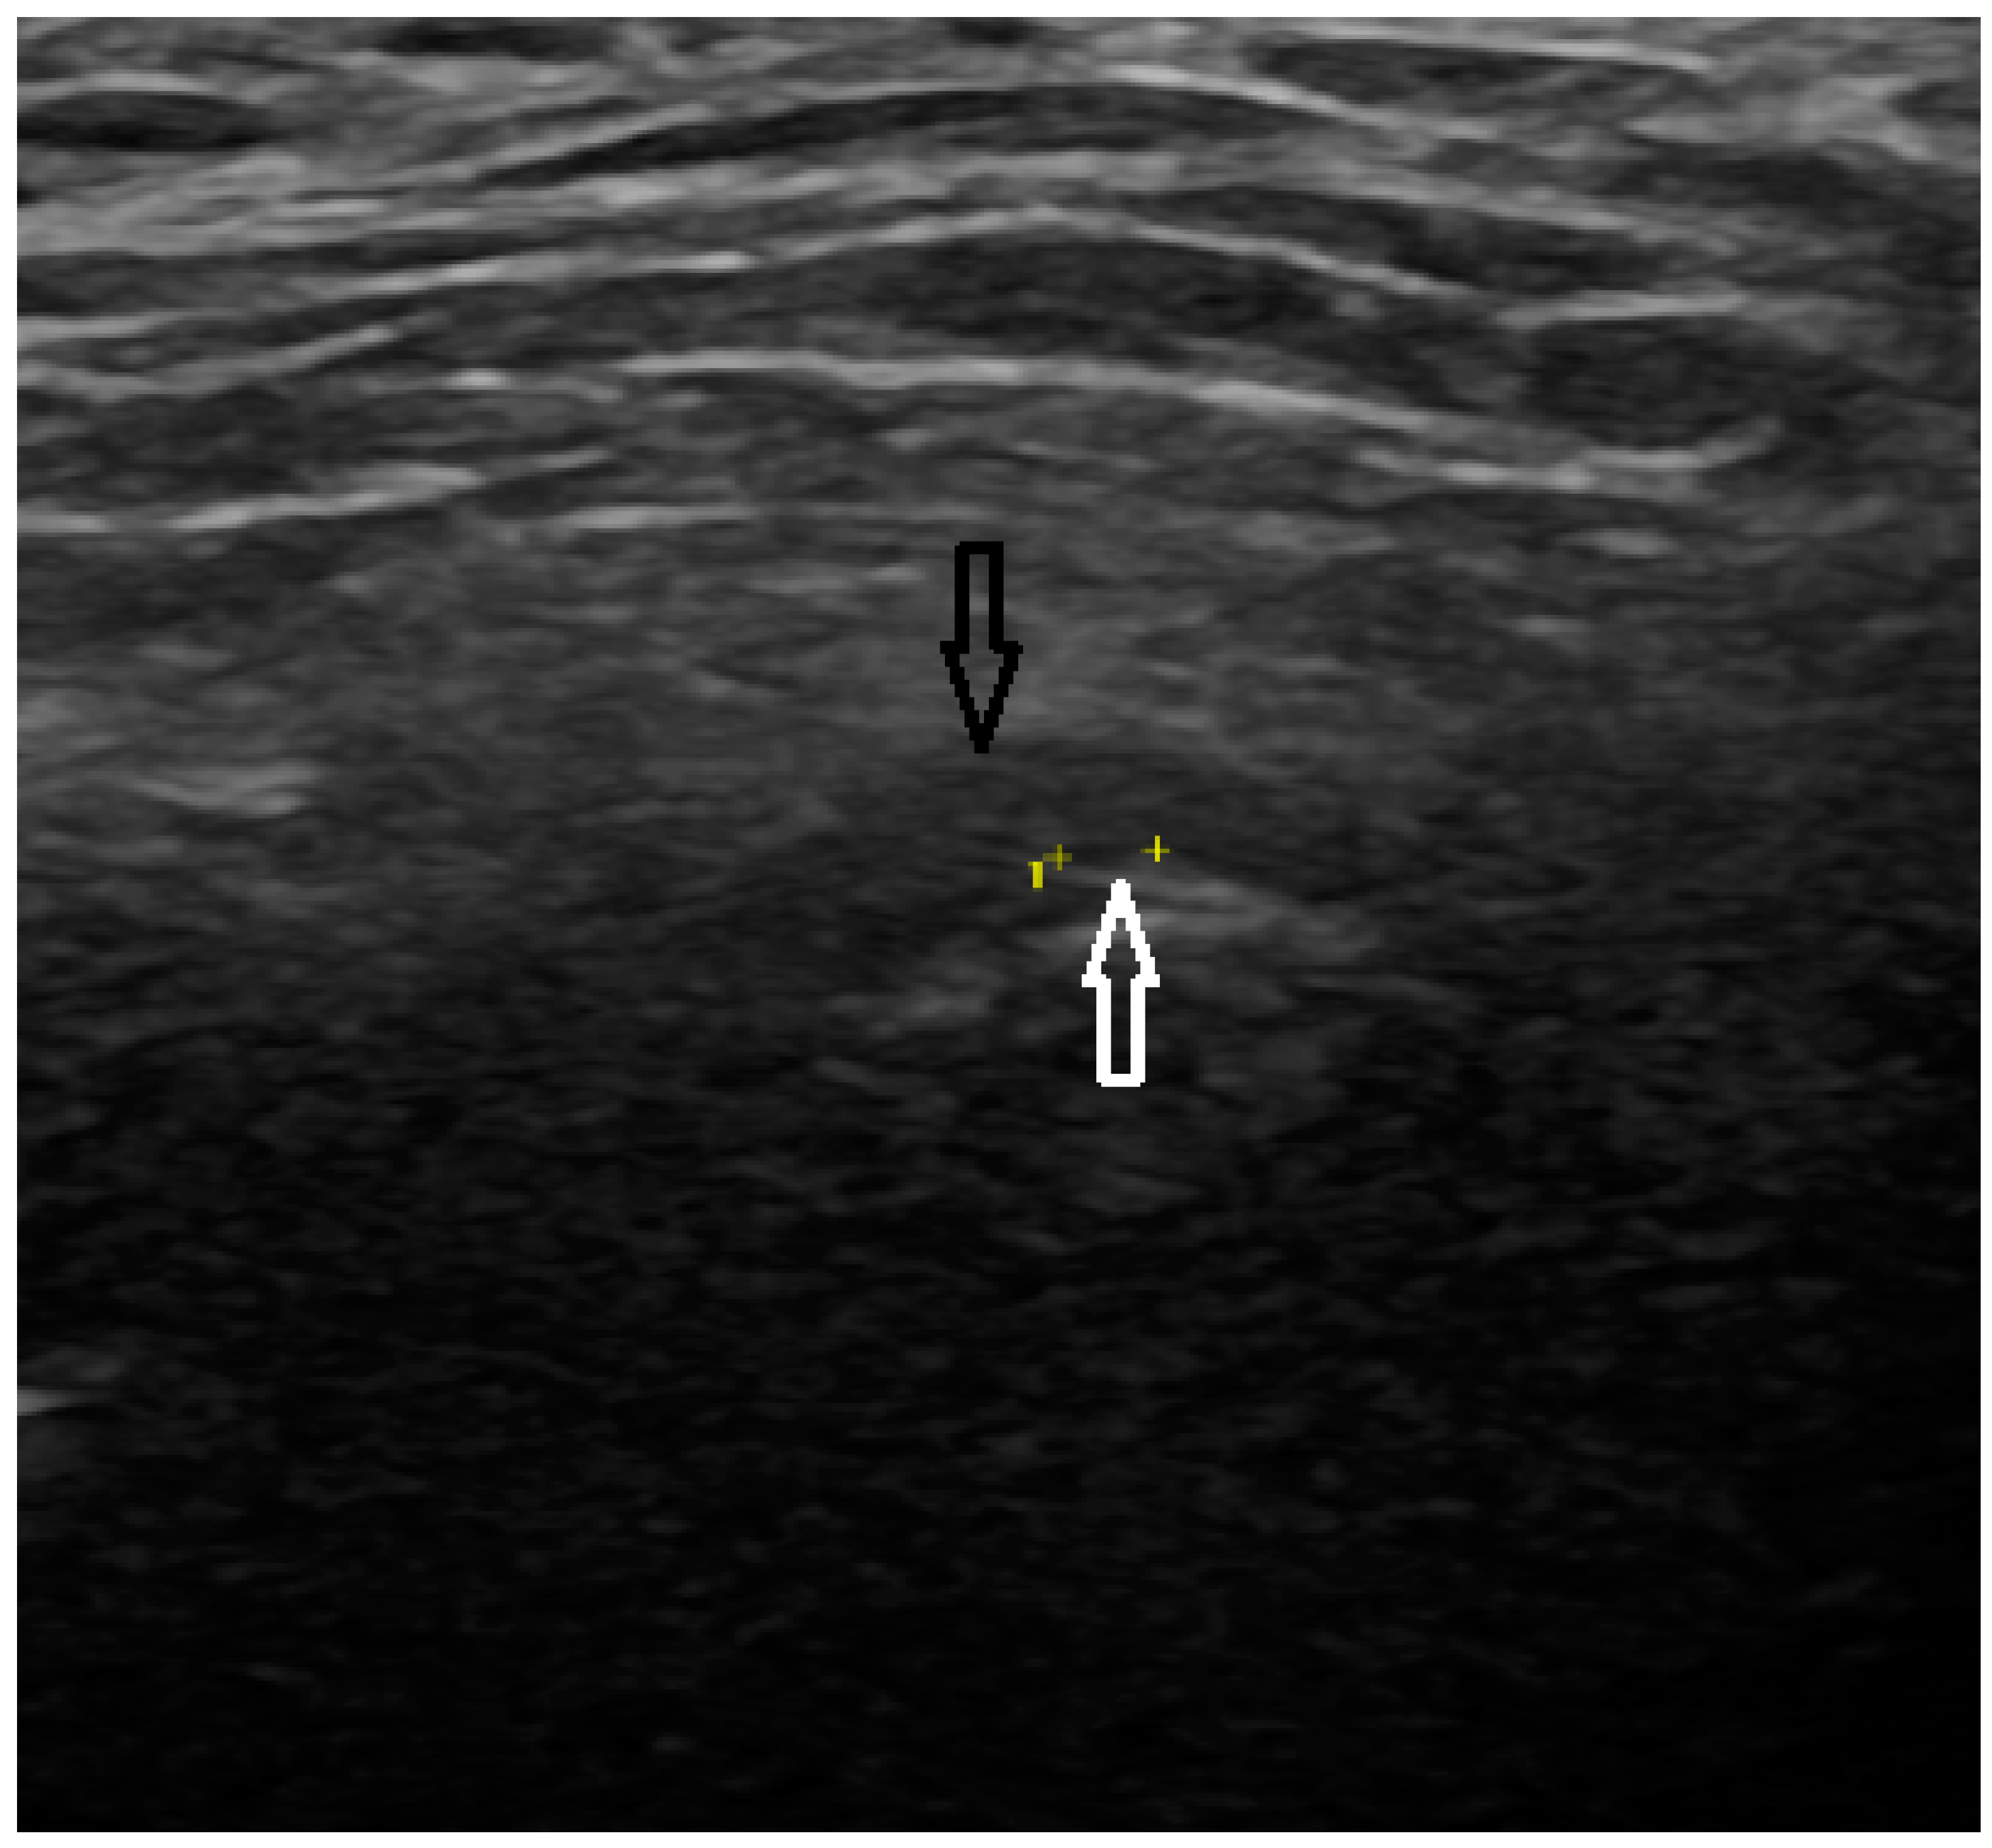

In the CBCT analysis, a comprehensive assessment was conducted on the morphology of the condylar process. This evaluation adhered to established diagnostic criteria aimed at identifying various pathological changes. Specifically, the analysis included the detection and characterization of osteophytes or erosions, indicating localized bone loss or damage, and the presence of cystic formations was evaluated (Figure 1). The study involved a detailed examination of the bone structure itself. This included assessing regions for possible rarefaction or densification. The evaluation extended to the measurement of the joint space width. The condylar fossa and the articular tubercle were also assessed. All CBCT examinations were performed in layers 0.2 mm thick, with 90 kV and 40 mAs using a Carestream CS 9300 (Kodak Dental Systems, San Francisco, CA, USA).

Figure 1. CBCT scan (black arrow points to osteophyte).